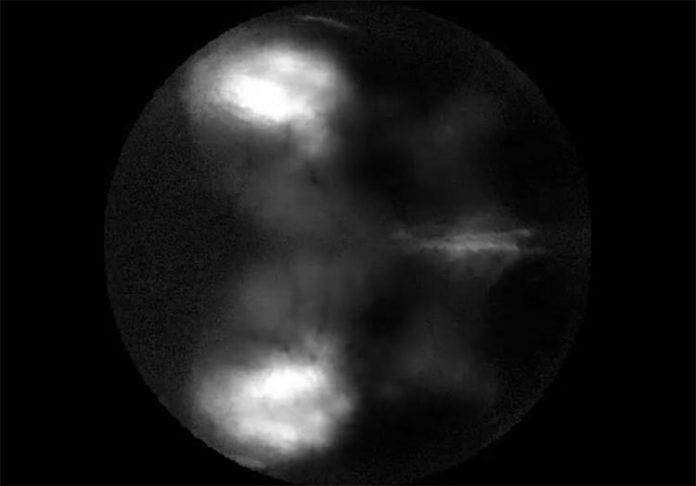

Este vídeo muestra la respuesta neural a los estímulos visuales que se mueven en un monitor enfrente del ratón, lo que resulta en una barra de actividad del córtex visual en ambos hemisferios cerebrales (la velocidad es un 2,5% mayor que el tiempo real) Crédito: Michaiel et al./Cell Reports